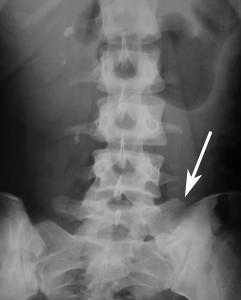

Переходный люмбосакральный позвонок при синдроме Бертолотти хорошо диагностируется при проведении рентгенографического исследования позвоночника пациента (или КТ/МРТ пояснично-крестцового отдела). На снимке можно увидеть явные признаки полного или неполного сращения поясничного позвонка L5 с крестцом и крыльями подвздошной кости.